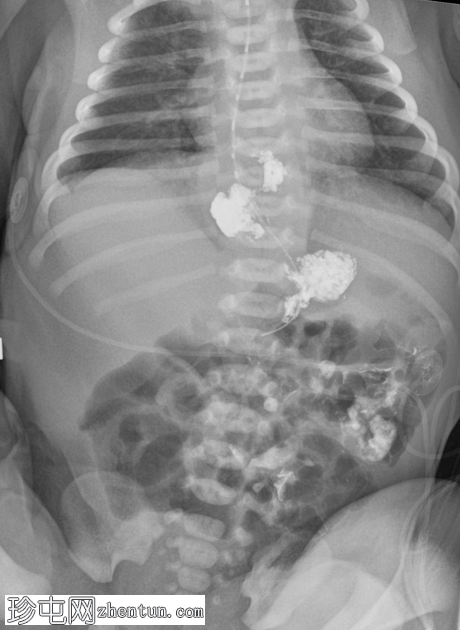

足月新生儿无法耐受任何喂养,经胃管/口服喂养后出现大量呕吐。评估是否存在肠旋转不良和胃排空障碍。

X线片

正位

胃部初始显影,并立即反流至食管裂孔疝。在其近端可见管径正常的远端食管。十二指肠降部和横部显影较弱,左上腹可见数段管径较小/部分减压的近端小肠显影。

延迟1小时拍摄的X线片显示食管裂孔疝和胃部仍有造影剂残留,造影剂远端扩散受限,很可能是由于造影剂用量较少所致。充满气体的肠袢外观正常,乙状结肠内可见气体,直肠内未见气体。

这是一例儿童患者在透视下发现的食管裂孔疝病例。

最初的临床考虑是肠旋转不良,因为患者频繁且呕吐量大,但后来怀疑这是由中等大小的食管裂孔疝引起的。